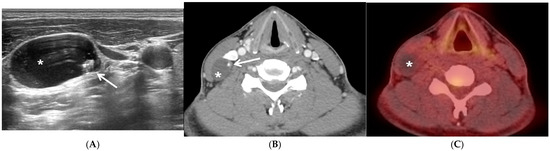

3.1. Representative Case of PTC in Solitary Lateral Neck Cystic Mass without Identifiable Primary Carcinoma in Thyroid